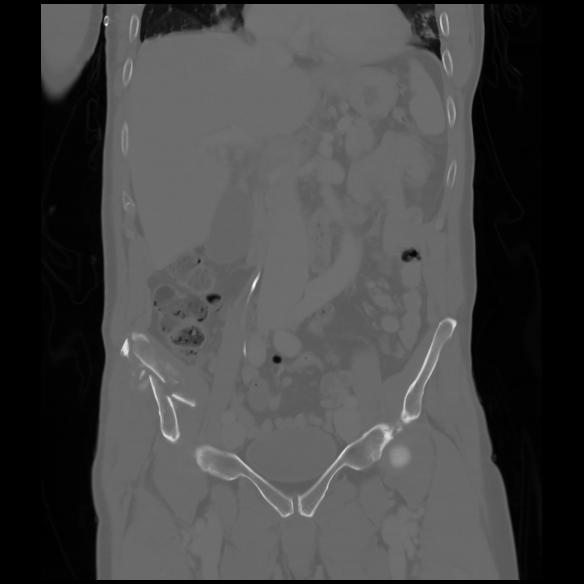

6 CUERPO,CE,Coronal,3.000,CUERPO,Coronal,